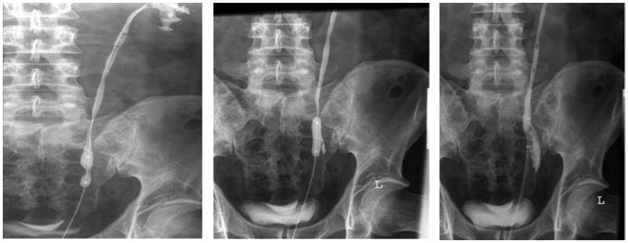

The patient population consisted of 8 men and 6 women; mean age was 59.2years (range 36-78years) at time of procedure. The causes of ureteral strictures were diverse (Table 1). In 12 patients, Acucise® was the primary treatment. The other two patients had already been treated with balloon dilatation and/or stent placement (double-J catheter) elsewhere. Five patients had more than one stricture ipsilaterally. A total of 21 strictures were treated, of which 6 were located in the proximal ureter, 7 in the mid-ureter and 8 in the distal ureter. Only strictures ≤2cm were treated with Acucise endoureterotomy. The stricture was treated until the hourglass-shaped figure of the balloon catheter disappeared and extravasation of contrast was visible (Figure 1). After visualization of extravasation, a 7-8 French double-J catheter was placed for 6weeks.

Figure 1 The Acucise® procedure

a) Retrograde pyeloureterography

b) Balloon placement and inflation

c) Acucise® ureterotomy with contrast extravasation, followed by placement of a double-J catheter.